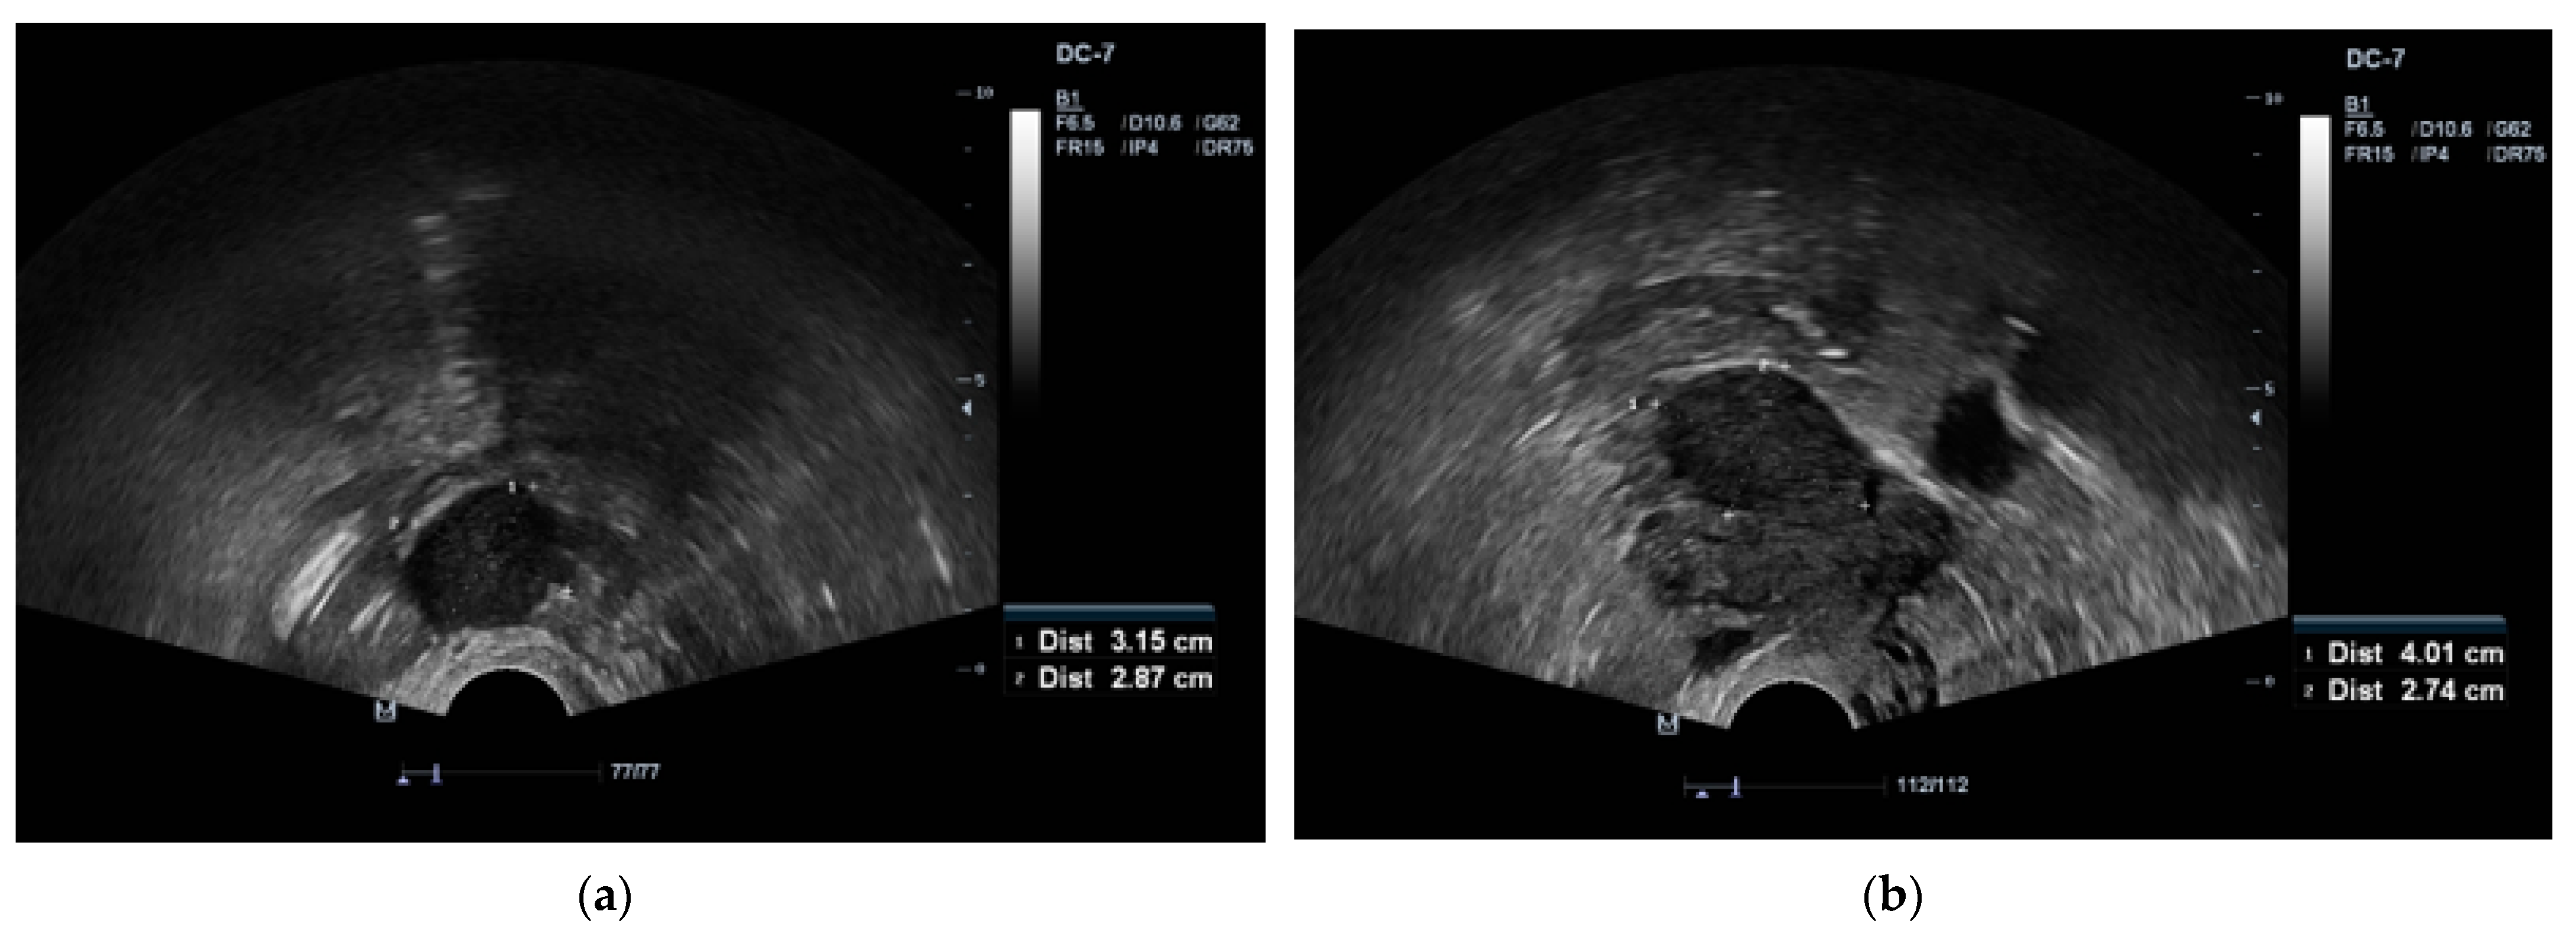

Subsequently, the patient was referred to the gynaecology department due to suspected ovarian tumors of unknown aetiology. Ovarian tumor markers were conducted for the patient and they were within normal ranges (cancer antigen 125 (CA-125) 25.5 kU/L (normal range, <35) and human epididymis 4 (HE4) 31.6 pmol/L (normal range, <140)). A pelvic MRI confirmed the presence of two low-intensity masses in ovaries bilateral, with the left mass measuring 1.9 × 1.9 cm and the right mass measuring 2.1 × 2.6 cm (Figure 2). Additionally, a small amount of free fluid in the pelvis was observed.

Figure 2. Pelvic magnetic resonance imaging (MRI) of two ovarian lesions. The pelvic MRI revealed a circumscribed left ovarian structure measuring 1.9 × 1.9 cm and a circumscribed right ovarian structure measuring 2.1 × 2.6 cm.